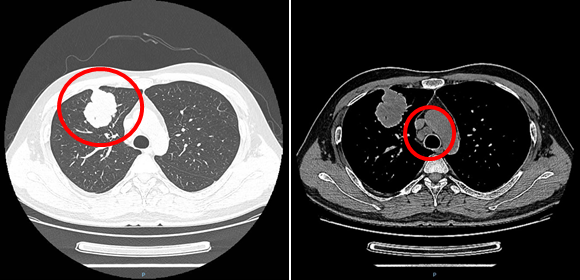

CT(2020-11-24):右肺上叶前段可见团块状软组织密度影,边界不清,边缘可见分叶及毛刺,大小约51mm*51mm*41mm,右肺上叶前段支气管远端闭塞,病灶牵拉邻近胸膜;纵隔内气管旁见肿大淋巴结,最大径约22mm。

CT提示右肺上叶前段有最大径约51mm肿块,纵隔内气管旁有肿大淋巴结

2021-11-24 化疗前

2021-12-23 化疗后

培美曲塞+卡铂化疗1周期后复查,右肺上叶病灶及纵隔淋巴结处于稳定SD状态